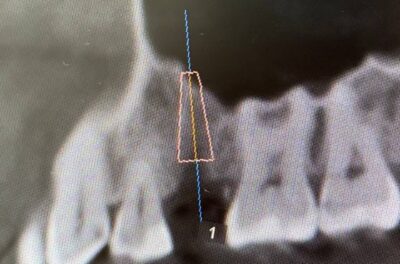

Специализация: терапия(эндодонтия), ортопедия, имплантология.